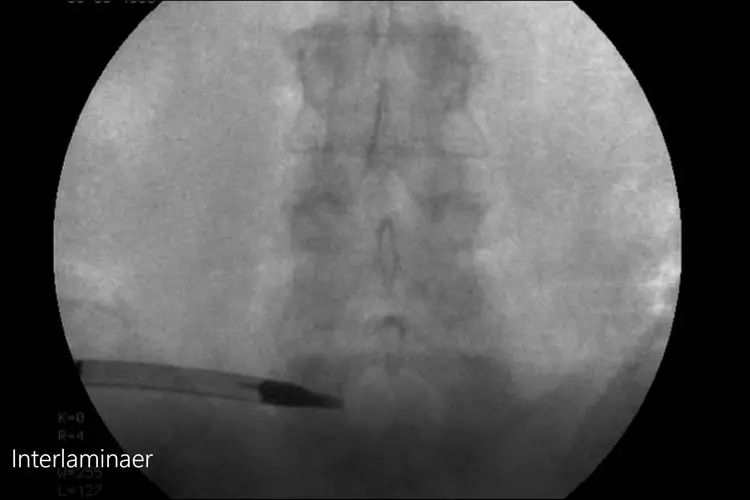

第一步C臂定位腰5骶1,全程只透视一次。手术的切口只有6毫米左右。